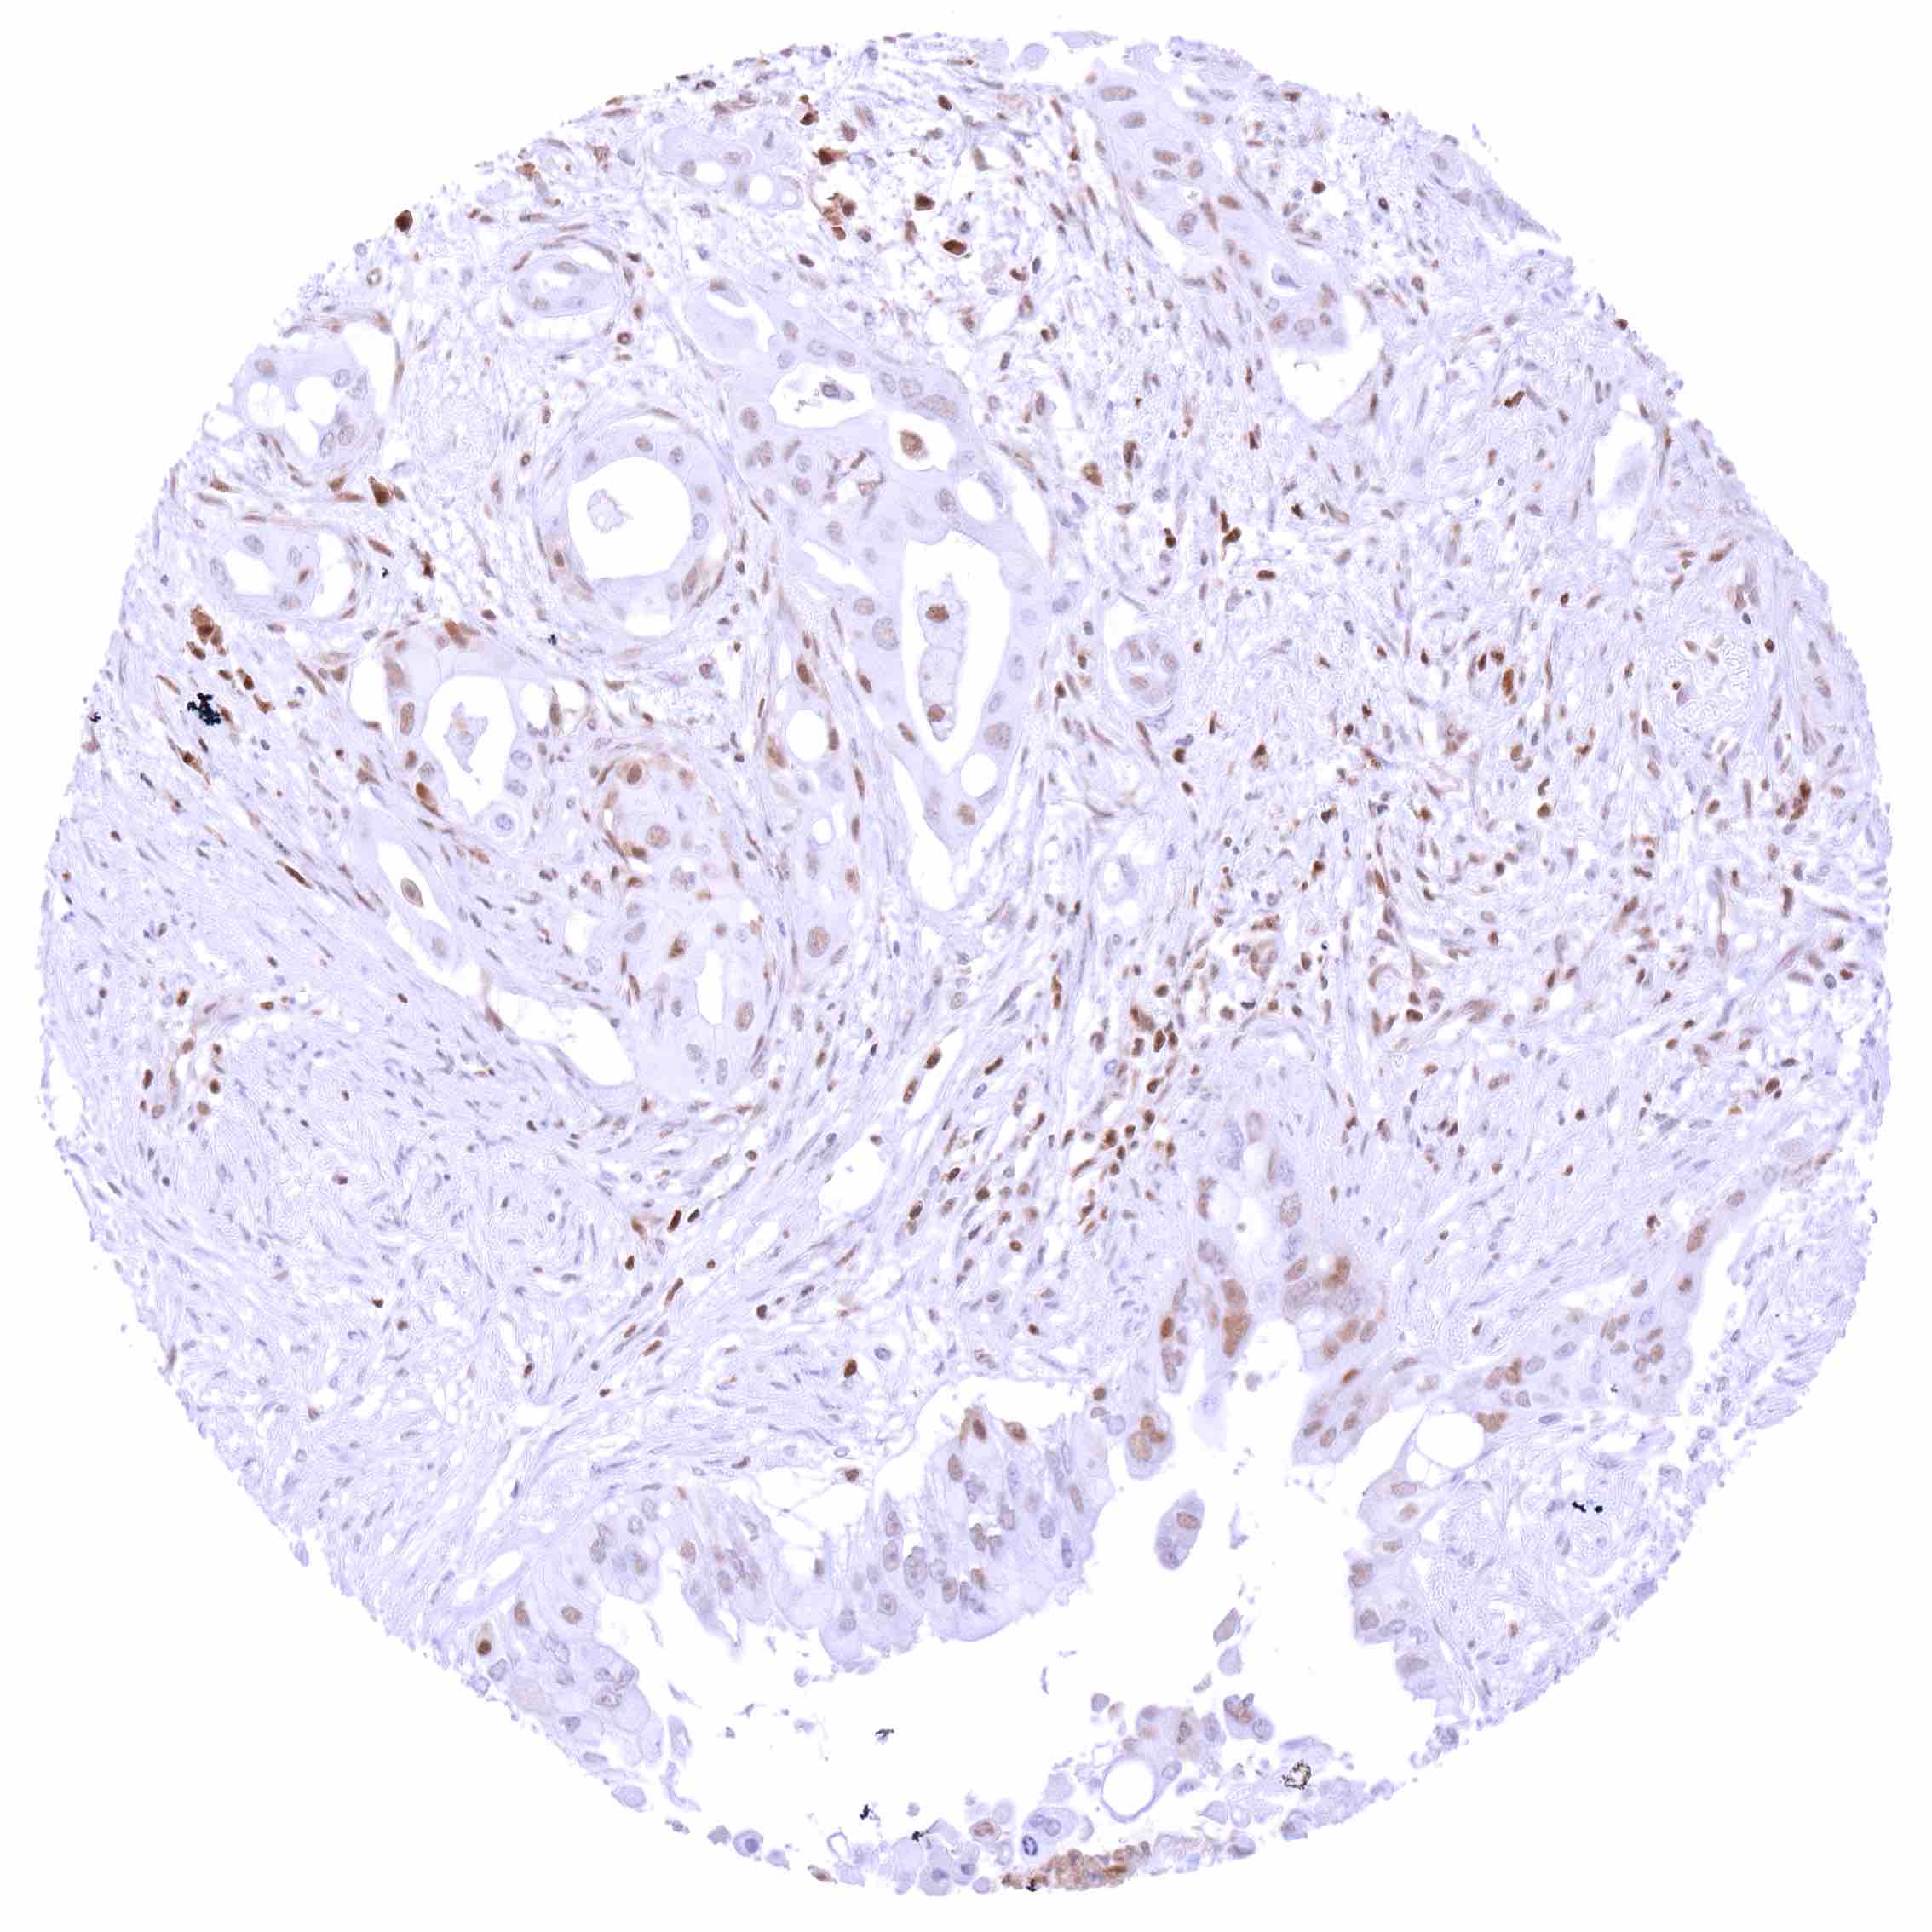

Pancreas – Ductal adenocarcinoma with weak to moderate, predominantly nuclear p27 staining of few tumor cells.